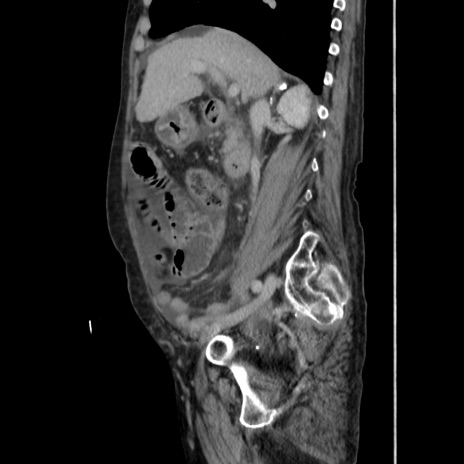

症例31(矢状断像)

【症例】80歳代 女性

【主訴】腹部膨満感

【現病歴】他院にて肝硬変にてフォロー中。1週間前から便秘、腹部膨満感、臍部腫瘤あり受診となる。

【既往歴】肝硬変

【身体所見】腹部膨隆あり、皮膚変化なし、疼痛なし。

【データ】WBC 4600、CRP 0.25